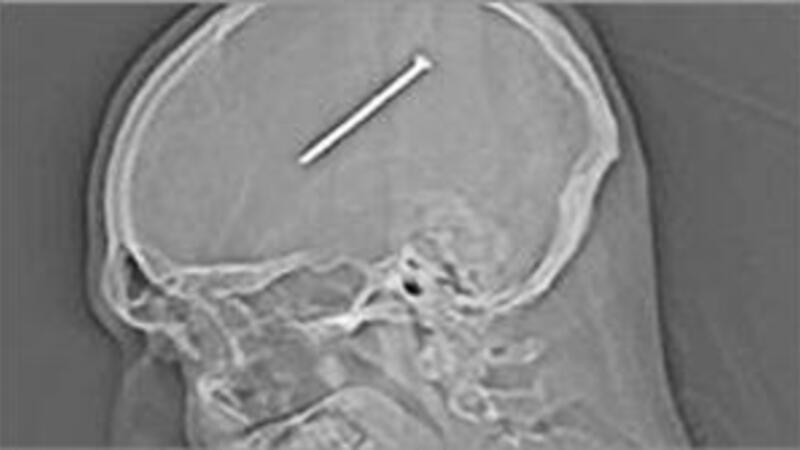

تمكن جراحون من اخراج مسمار بطول 8.25 سنتيمتر من وسط دماغ شخص من ضواحي شيكاغو، ضرب نفسه عرضا به.

وكان المصاب دانتي اوتيلو (34 عاما) يعمل في ورشته عندما ضغط عرضا على زر مسدس لتثبيت المسامير قرب رأسه، غير ان ما كان يجهله دانتي ان المسمار دخل رأسه، ولم يشعر بذلك حتى اليوم التالي عندما بدأ يعاني نوبات ترنح وعدم توازن.

وقال الاطباء لدانتي «ان المسمار كان على بعد ملليمترات فقط من منطقة حساسة جدا وسط الدماغ مسؤولة عن فعاليات حيوية مهمة».